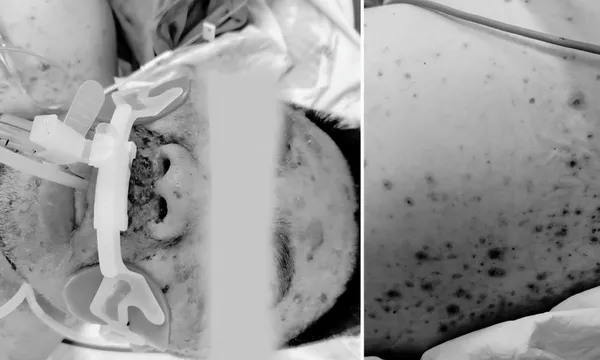

Dù đã được điều trị tích cực bằng thuốc kháng virus và các biện pháp lọc máu hiện đại, nhưng tình trạng suy gan tối cấp, suy đa tạng, rối loạn đông máu nghiêm trọng của bệnh nhân không được cải thiện.

Bệnh nhân có thể bị viêm não, viêm màng não - biến chứng thần kinh hiếm gặp nhưng cực kỳ nặng, có thể để lại di chứng vĩnh viễn hoặc gây tử vong; Nhiễm trùng da, mô mềm - các nốt thủy đậu bị bội nhiễm vi khuẩn gây viêm mô tế bào, áp xe, thậm chí là nhiễm trùng huyết; Hội chứng Reye - một biến chứng cực kỳ nguy hiểm, thường gặp ở trẻ em dùng aspirin khi mắc thủy đậu, gây tổn thương gan và não.

Ở phụ nữ mang thai, thủy đậu có thể gây dị tật thai nhi hoặc thủy đậu bẩm sinh. Và như trường hợp trên, thủy đậu có thể dẫn đến suy đa phủ tạng, rối loạn đông máu, tử vong, đặc biệt ở những người có bệnh nền hoặc hệ miễn dịch suy yếu.